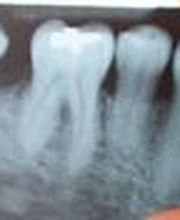

Il dottor Mario Roggerone, medico chirurgo odontoiatra, si occupa personalmente di tutte le diverse specialità eseguite dal centro, dove vengono praticati i seguenti interventi specialistici: endodonzia conservativa, paradontologia, protesi fisse e mobili, chirurgia dentale. Inoltre, il dottore pratica periodicamente ai suoi pazienti tutte le procedure di prevenzione dentistica e di igiene orale quali ad esempio: la detartrasi e i trattamenti sbiancanti, che sono all'ordine del giorno e vengono sempre praticate da un professionista accreditato. Potete contattare il nostro centro per ogni richiesta e per prenotazioni al nostro numero. Il dottor Roggerone sarà sempre disponibile anche per una visita a domicilio per ritirare la vostra protesi o su appuntamento. Lo studio del dottor Roggerone è a Piacenza in v. Chiusa.